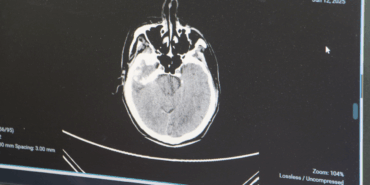

Gençlerde Beyin Kanaması Artıyor: Dikkat!